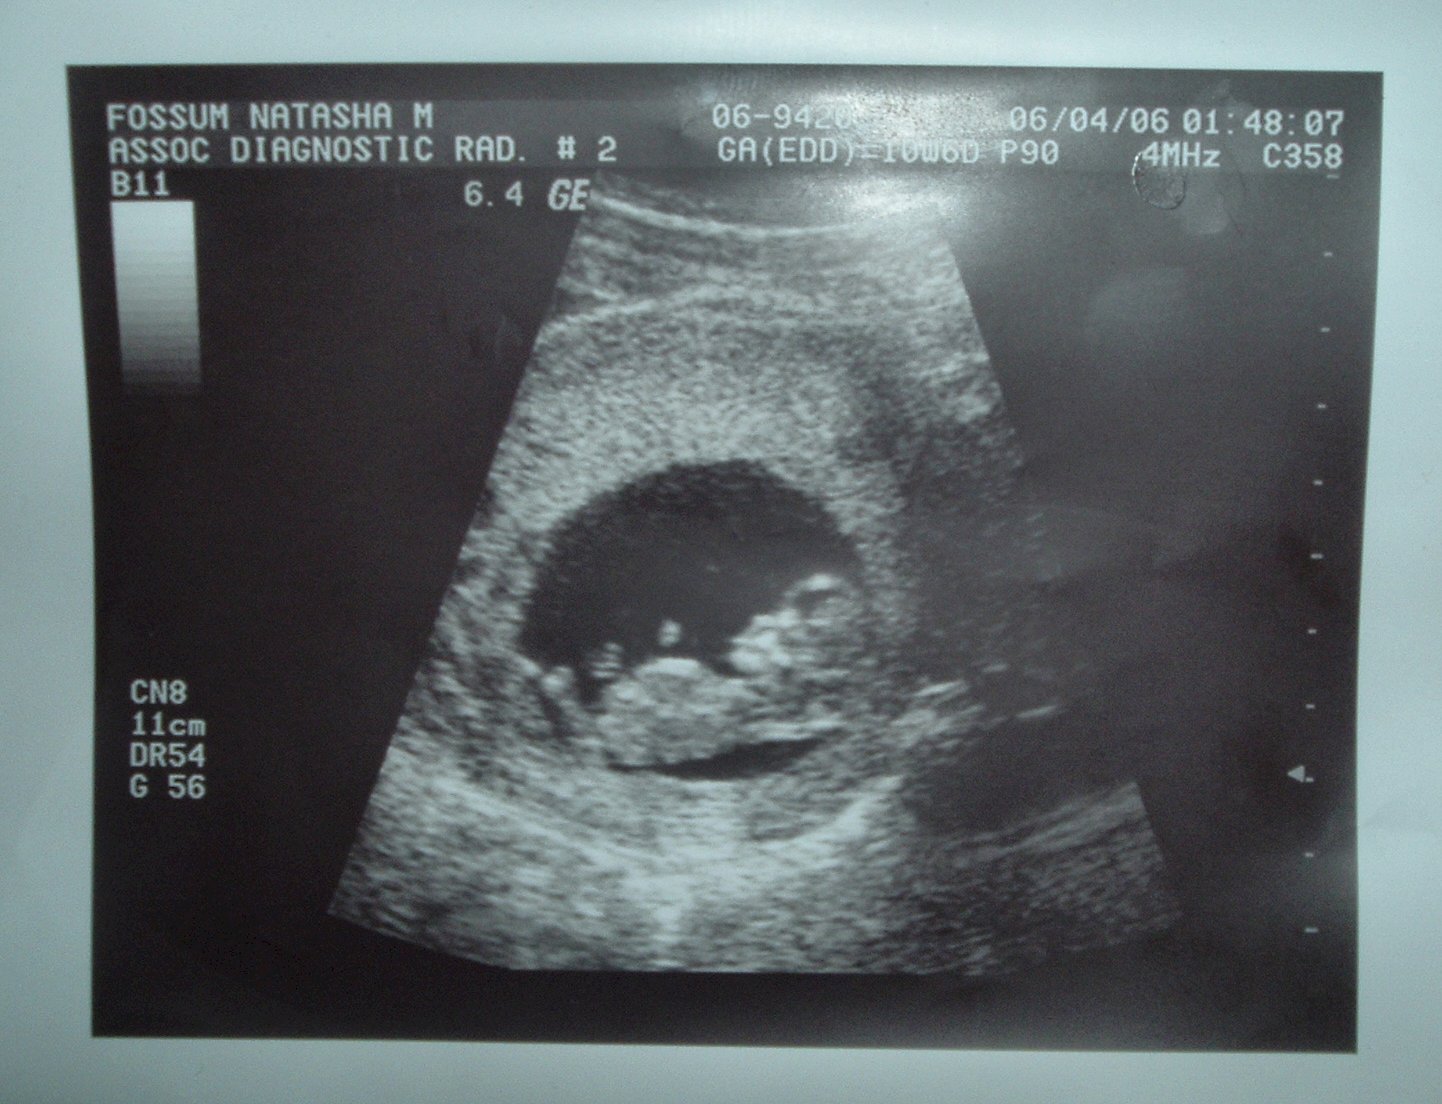

In January, I took 5 tests and in February I took 2. All came back negative so I thought I was just missing my cycles due to stress. Well, a couple weeks ago, I took another test since I was having tons of pregnancy symptoms - I got a DARK positive! I had an ultrasound done and I heard and saw the heartbeat! This is very exciting since we were only trying to concieve since October. I have attached a picture of my little baby...